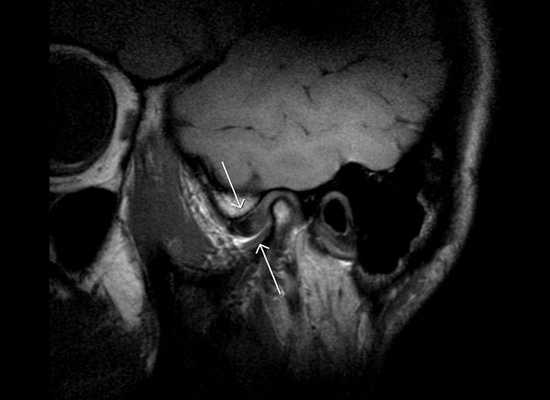

Пациентка жаловалась на эстетический дефект (выступающие клыки), затруднённое пережёвывание пищи, травму слизистой из-за накусывания щеки и губ и боли в области височно-нижнечелюстного сустава при широком открывании рта.

Несколько лет назад дискомфорт в области височно-нижнечелюстного сустава и раздражение слизистой стали усиливаться. Девушка принимала обезболивающие препараты, но они помогали ненадолго.

- Магнитно-резонансная-томограмма височно-нижнечелюстного сустава (МРТ ВНЧС).

При перекрёстном прикусе часто нарушается движение нижней челюсти и функции височно-нижнечелюстных суставов, особенно в случае аномалии прикуса со смещением нижней челюсти в сторону.

При открывании рта может возникать хруст и боль. Иногда нижняя челюсть блокируется и её движение в поперечной плоскости затрудняется. Это ведёт к неравномерному распределению нагрузки на зубы в момент жевания, а со временем — к травматической окклюзии (неправильному контакту одной челюсти с другой) и заболеванию тканей зубов и пародонта.

Изменения в височно-нижнечелюстном суставе

При нарушении функций или ограничении подвижности головок и суставных элементов развивается гипомобильность сустава, нарушается трофика его тканей. В зависимости от индивидуальных особенностей организма это может приводить к смещениям диска, появлению болей, хрустов и щелчков в суставе, а позже — к атрофии и деформации диска и суставных поверхностей [1] [2] .

Наблюдение за характером движений суставов, функциональные пробы и рентгенологические исследования (особенно ортопантомография) позволяют обнаружить осложнения со стороны височно-нижнечелюстного сустава и мышечной функции [4] [7] [8] [9] [12] . По показаниям проводятся КТ и МРТ данной области в положении открытого и закрытого рта.